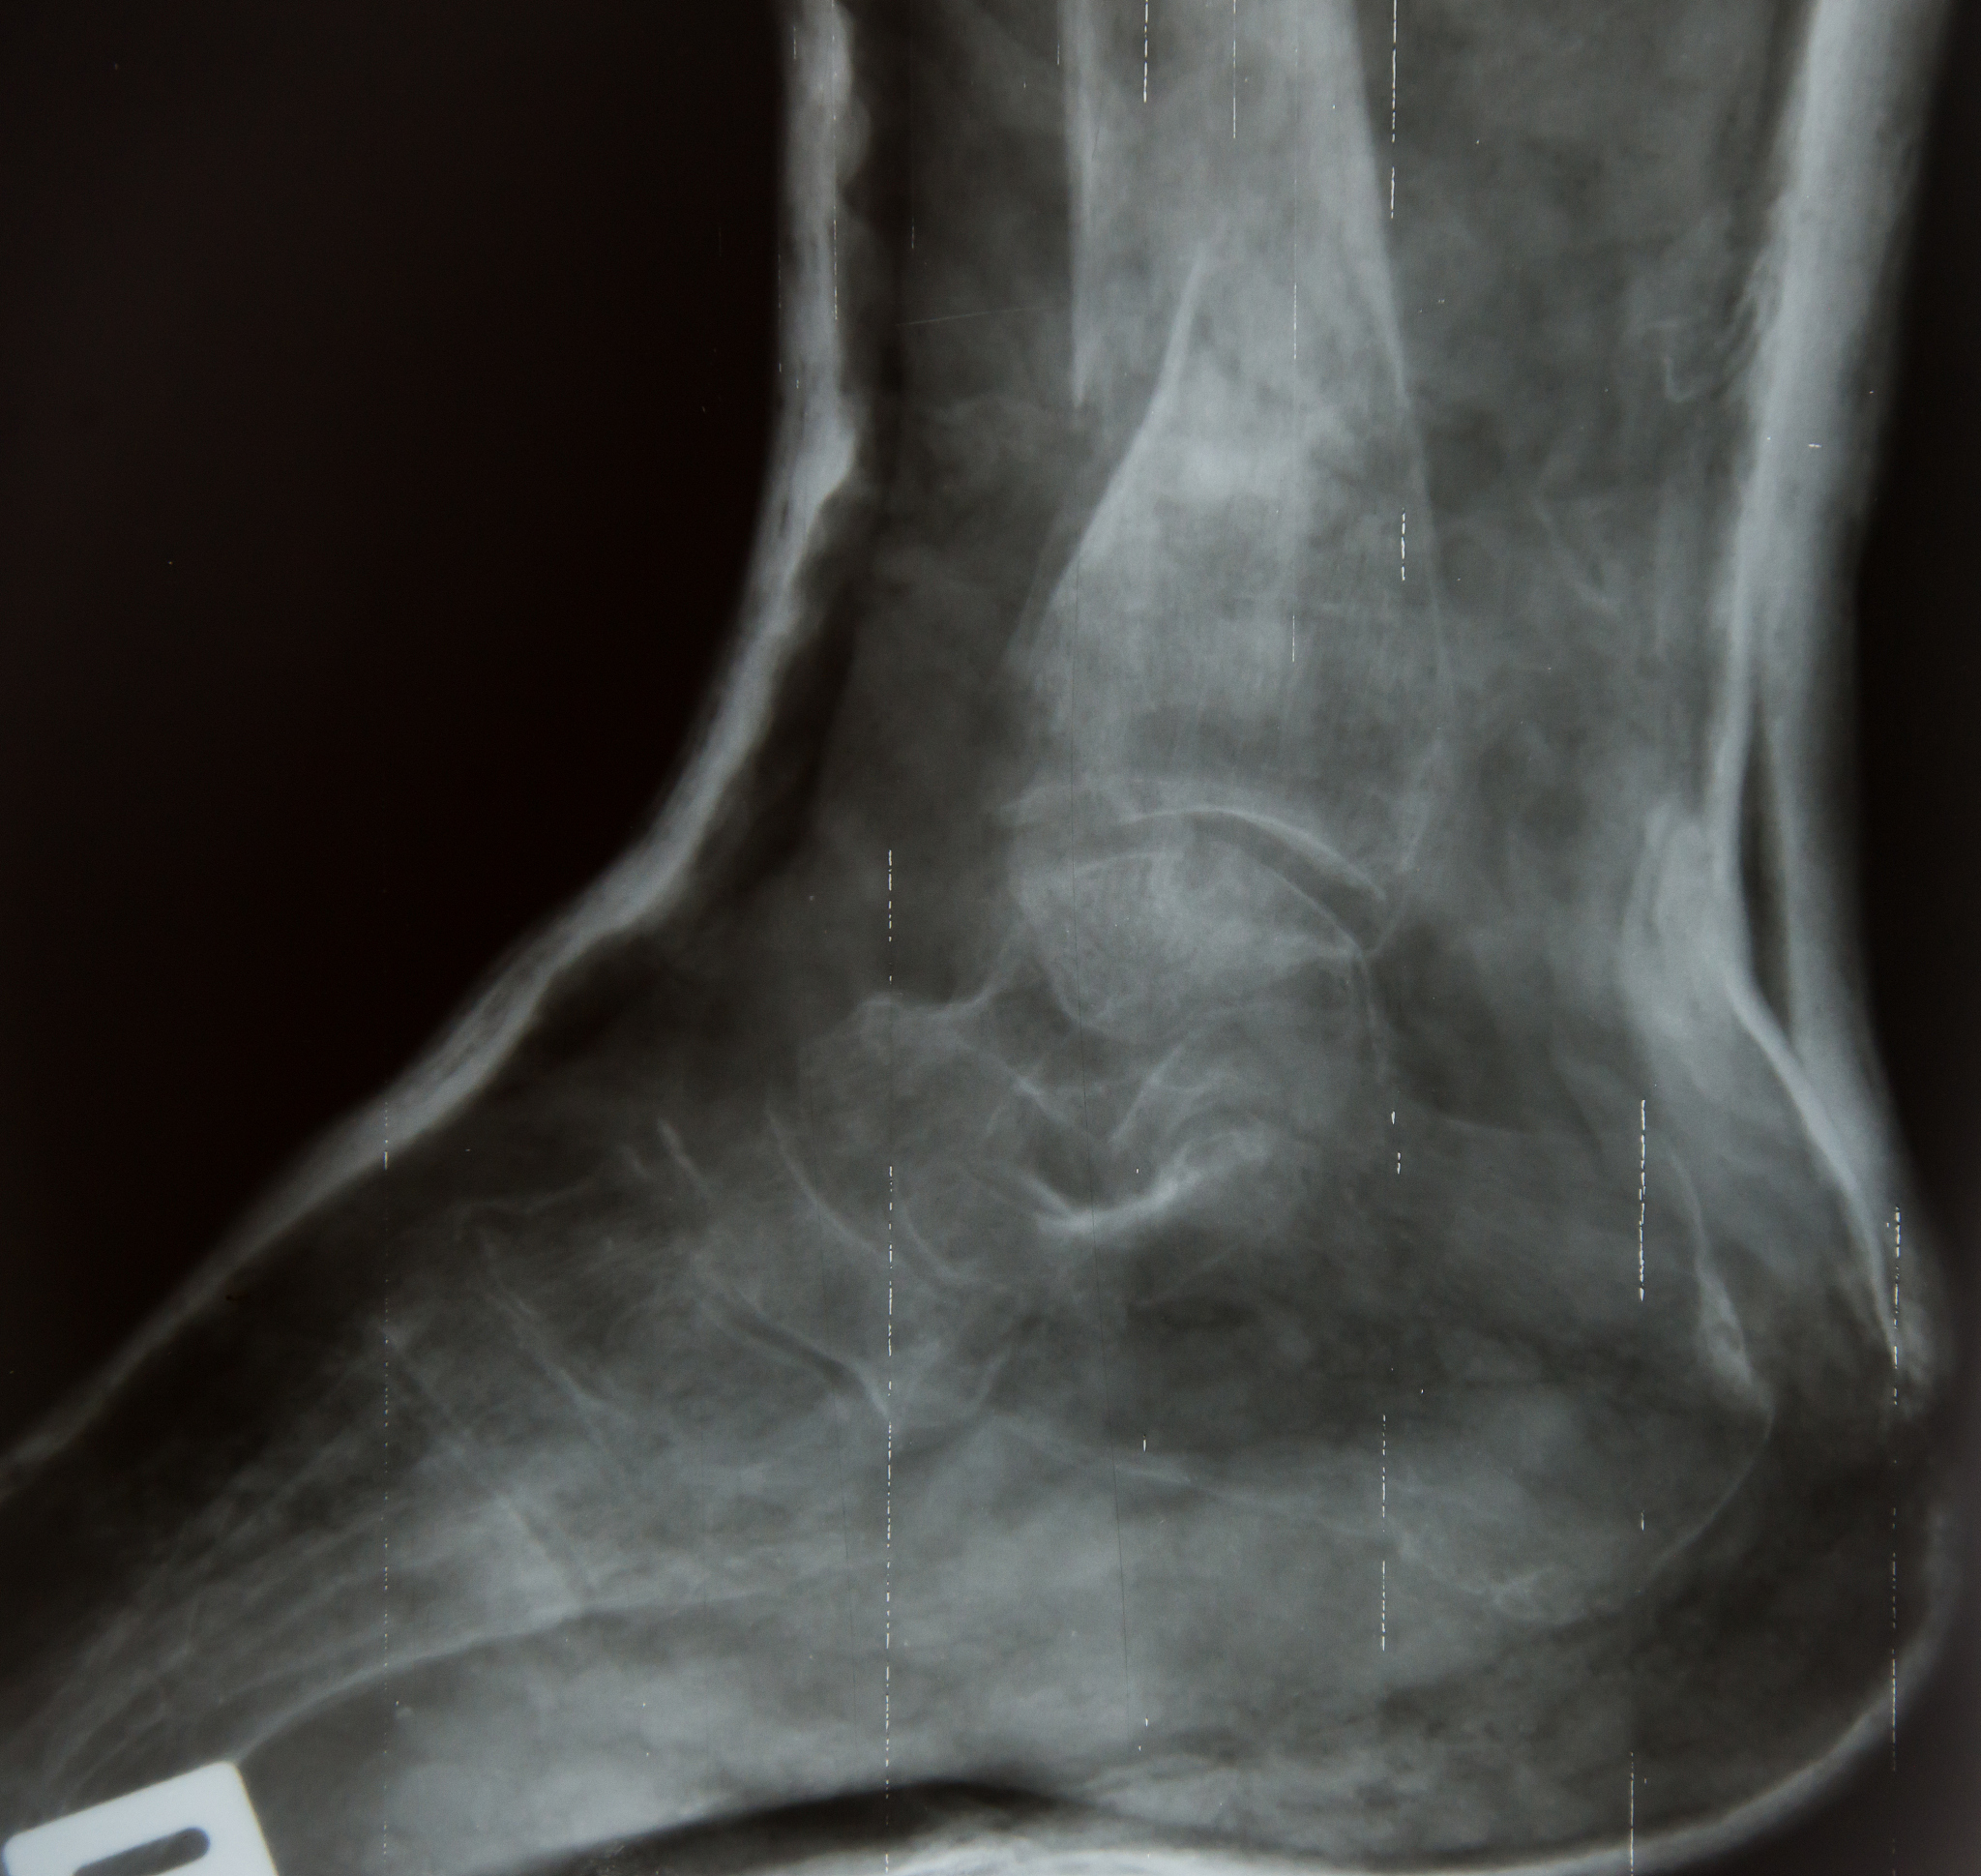

手术的目的是修复踝关节外侧副韧带复合体的连续性,使其能限制踝关节活动时距骨的过度内翻和前移,以防止继发关节内软骨损伤和其他并发症的发生。